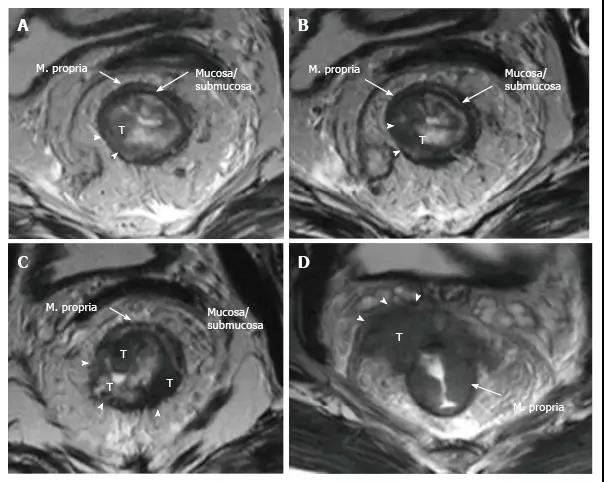

在 T2 加权成像中,固有肌层处于高密度直肠系膜脂肪和粘膜/粘膜下层之间,显示中度至轻度高信号。T2 加权图像上的直肠肿瘤的信号强度通常介于固有肌层和粘膜的信号强度之间(图 8)。

T1 肿瘤局限于粘膜下层,T2 肿瘤向下延伸但不超过肌层,非相控阵线图条件下或直肠内超声下 T1 与 T2 的区分并不可靠,肿瘤可直接分作 T1/T2。肿瘤超过肌层并延伸入直肠系膜脂肪时称为 T3,肌层受累时如果有穿透血管不要误将其划作 T3(图 8 和图 9)。

图 8. 直肠癌 T 分期。美国癌症联合委员会根据侵润深度进行 T3 肿瘤的分层:小于 5 mm,T3a;5~10 mm,T3b;超过 10 mm,T3c。

图 9. 直肠癌 T 分期磁共振成像。T2 加权轴向图像显示不同 T 阶段的直肠癌:A. T1 肿瘤局限于粘膜下层,尚未进入固有肌层(箭头);B. T2 肿瘤扩展到但不超出固有肌层(箭头);C. T3 肿瘤超出固有肌层和并延伸入直肠系膜脂肪(箭头);D. T4a 肿瘤侵入内脏腹膜(箭头)。

壁外侵犯深度指肿瘤超过肌层的延伸,美国癌症联合委员会建议根据壁外侵犯深度将 T3 分层:T3a<5 mm,T3b 5~10 mm,T3c>10 mm。T3a 者生存率更高,这些早期 T3 肿瘤单独手术就可控制,与 T1/T2 肿瘤预后相当。T4 肿瘤延伸至脏层腹膜表面或邻近结构(表 1,图 8 和图 10)。